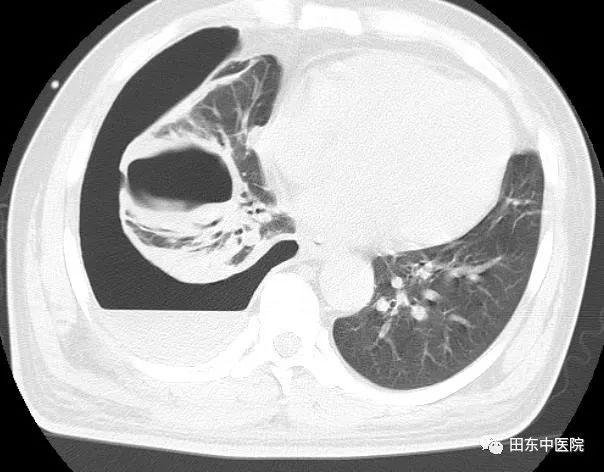

中午12点,一位体型肥胖病人走进了医生办公室,刚好交班结束的我接待了他,他自诉已胸痛了10天有余,先前因腰痛一直在院外治疗,没有好转遂到我院进行进一步的检查。详细了解完其病史后,我为其完善了体格检查:右侧胸胁部疼痛,呈持续性胀痛,有胸闷、呼吸困难,发热畏寒。查体见双侧呼吸运动不对称,两侧触觉语颤不对称,右肺叩诊浊音,右肺呼吸音消失。结合先前他在门诊做过的B超及后续补充的胸部CT结果,发现病人右侧胸腔有大量积液,为了解积液性质及缓解积液对肺脏的压迫,遂给病人行胸腔穿刺置管术,把胸腔里的积液引流出来。过程很顺利,术中抽出了约5000ml伴有腐臭气味的咖啡色脓液,术后病人的疼痛症状得到了极大的改善。

抽出的

脓液